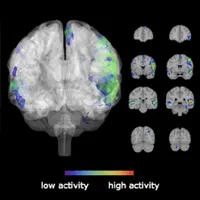

Neuroscience

Cognitive

Science

Science